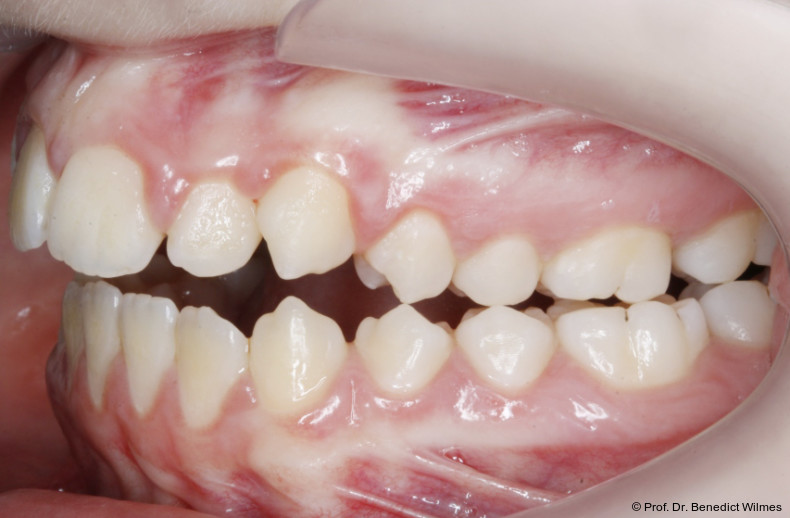

Eine 13-jährige Patientin stellte sich mit beidseitigem Kreuzbiss, einem anterioren offenen Biss und einer Angle Klasse II vor. Das viszerale Schluckmuster wurde mittels logopädischer Maßnahmen umgestellt, der offene Biss persistierte jedoch (Abb. 3a–l).